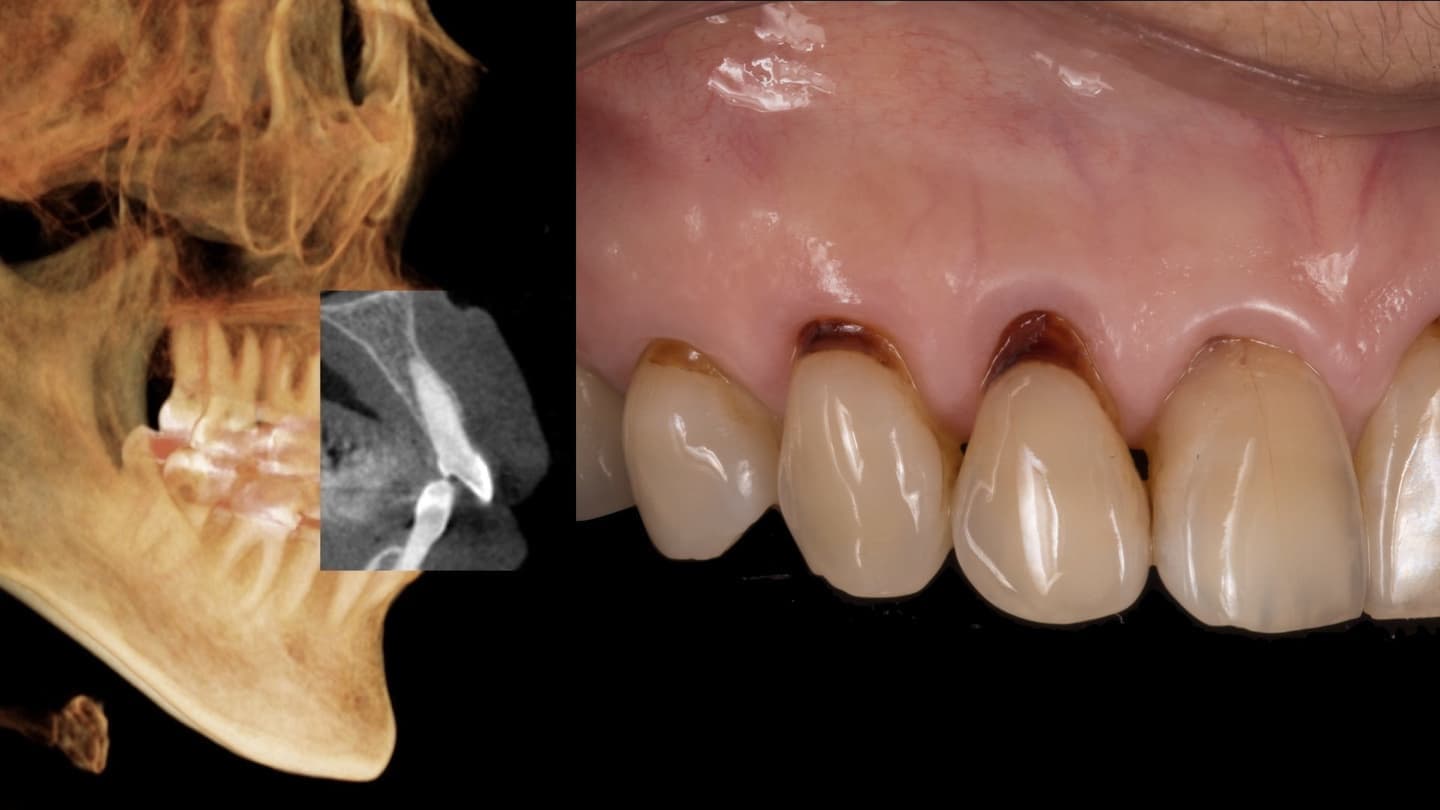

あらゆる検査からの情報を分析します

基本的な検査だけでなく、CT検査、歯周病に特異的な細菌のPCR検査、噛み合わせの検査、生活習慣の見直しなどを行います

専門医ではないと対応できない症例もあります